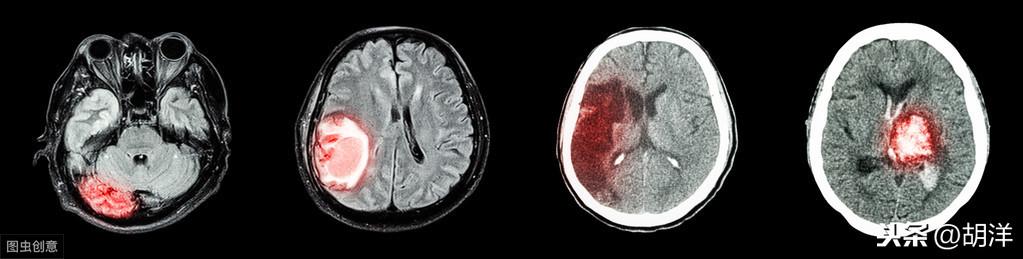

脳卒中の前兆または後遺症

脳卒中とは、西洋医学でいう脳血管障害のことである。日常生活でも、脳卒中の後遺症で片側の手足が動かしにくくなっている患者をよく見かける。脳梗塞の原因は、高血圧、血中脂肪の濃さ、高コレステロールなどが関係することが多く、発症年齢は40歳以上が多い。

脳卒中の発症前には、めまい、頭痛、片側の手足のしびれ(手のしびれを含む)などの前兆症状がある。脳卒中の前兆としての手足や四肢のしびれは、ほとんどが気血の不足で皮膚を滋養できないことに関係しています。

もちろん、脳卒中後遺症の患者には、しもやけ、ヘルニア、手足のしびれなどの症状も見られるが、その多くは風痰・気滞、気虚・血滞、気虚・瘀血、肝虚・腎虚、組織・皮膚の栄養不足が関係している。

実際、現代医学では、ハンセン病、足ハンセン病、脳卒中による手足のしびれなどは、高血圧、高脂血症、動脈硬化、脳梗塞、脳出血などによる血液循環障害や血液供給不足がほとんどを占めている。

3.脳卒中 突然の片側の手足のしびれは、一過性脳虚血発作(TIA)、脳梗塞、脳出血などの急性脳血管障害に注意すべきである。脳卒中患者の多くは、脳卒中になる前に頭痛、めまい、手足のしびれ、舌の腫れなどがあることが多い。手指のしびれ」はよく見られる症状の一つです。特に高齢で、過去に高血圧や高コレステロール血症があった患者さんには注意が必要です。

(2) 脳卒中の前兆。脳卒中患者の多くは、脳卒中発症前に手のしびれ、腕の脱力感、一過性のめまいなどの症状があり、脳卒中発症後は口や目が不自由になり、片側の手足が不自由になるなど、様々な症状が現れます。

- 4.脳梗塞:脳は人体の司令塔であり、人間の運動や感覚などをコントロールする役割を担っているため、脳梗塞の場合、関連する神経を破壊して手のしびれを引き起こす可能性がある;

第一に、脳血管障害である。

脳血管疾患は中高年に多く、主に血管の硬化や狭窄が原因で、脳への血液供給が不十分となり、脳機能に影響を及ぼし、脳の神経支配部分にさまざまな機能障害をもたらす。

手のしびれは、脳への血液供給不足によって神経ジストロフィーが起こり、それが手足のしびれを引き起こす。